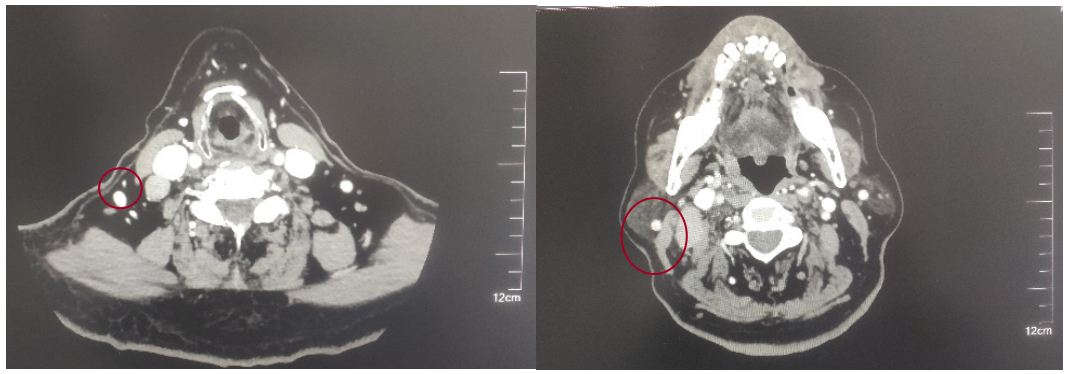

2022-05-05鼻咽部增强CT示:鼻咽CA并左侧翼腭弓、海绵窦受侵,伴邻近蝶窦、左侧筛窦、枕骨斜坡、左侧框下裂骨质破坏;右侧颈部多发肿大淋巴结(最大2.4×1.4cm),考虑转移;2.双侧梨状窝闭塞。

后患者至江苏省肿瘤医院放疗科就诊,2022-06-06完善头颅MR检查:

修正诊断:鼻咽癌T3N1M0,Ⅲ期。

2022-08-05(放疗近结束)复查MR,疗效评价:CR。鼻咽部肿物及咽后转移淋巴结颈部转移淋巴结均达到CR。